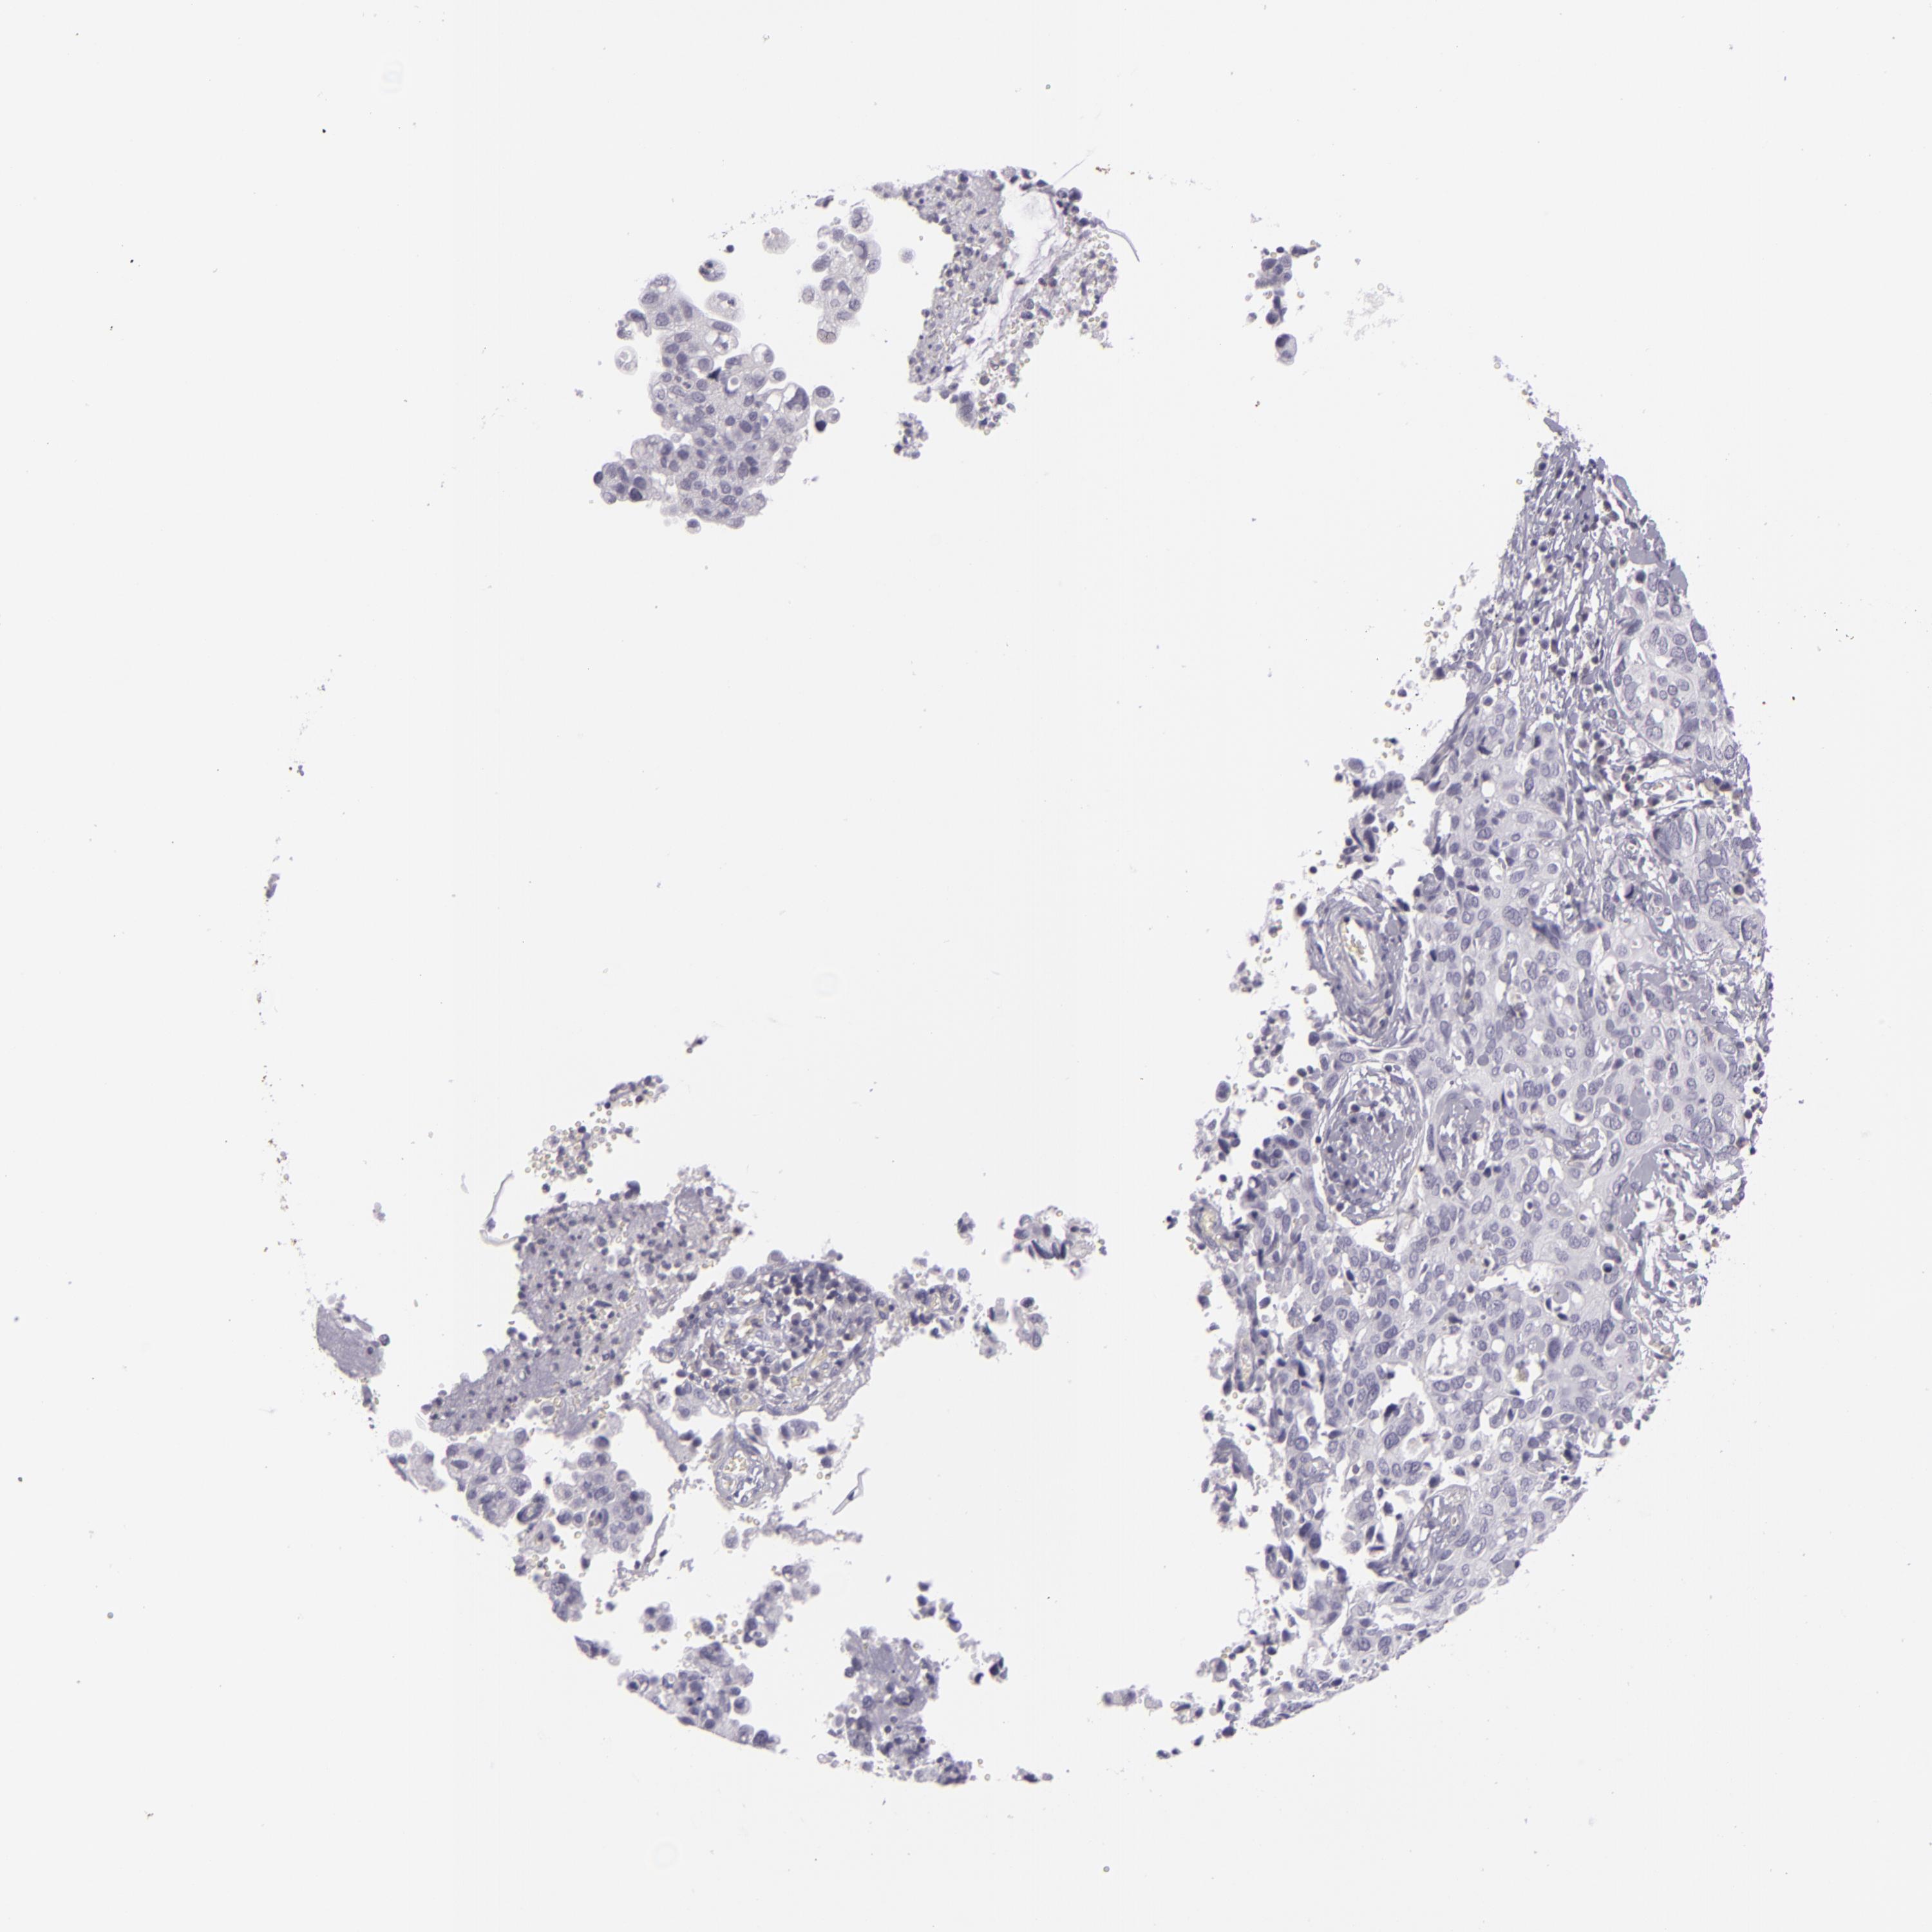

CERVICAL CANCER - Protein expressioni

A mouse-over function shows sample information and annotation data. Click on an image to view it in a full screen mode. Samples can be filtered based on level of antibody staining by selecting one or several of the following categories: high, medium, low and not detected. The assay and annotation is described here.

Note that samples used for immunohistochemistry by the Human Protein Atlas do not correspond to samples in the TCGA dataset.

Antibody stainingi

Antibody staining in the annotated cell types in the current human tissue is reported as not detected, low, medium, or high, based on conventional immunohistochemistry profiling in selected tissues. This score is based on the combination of the staining intensity and fraction of stained cells.

Each image is clickable and will lead to virtual microscopy that enables deeper exploration of all samples and also displays staining intensity scores, fraction scores and subcellular localization as well as patient and tissue information for each sample.

Antibody CAB001975

Staining

High

Medium

Low

Not detected

Intensity

Strong

Moderate

Weak

Negative

Quantity

>75%

75%-25%

<25%

None

Location

Nuclear

Cytoplasmic/membranous

Cytoplasmic/membranous,nuclear

Adenocarcinoma, NOS

Squamous cell carcinoma, NOS